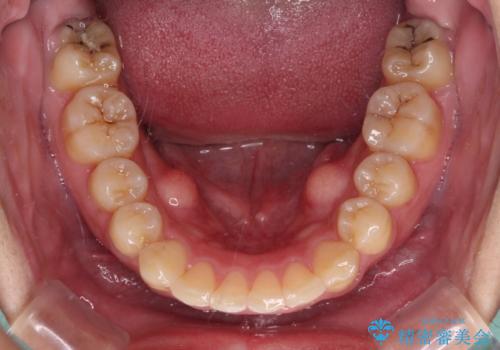

強い咬み込みですり減った前歯 デコボコを抜歯矯正で整える

咬合力が非常に強く、抜歯したスペースがなかなか閉じないであろうことは予想できましたが、思っていた以上に期間がかかりました。

前歯のすり減りも著しかったため、仕上げの位置の調整にも期間を要しました。